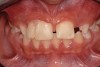

The patient saw her pediatric dentist for regular maintenance, returning to the orthodontist for yearly assessments until she reached the age of 12 years, 1 month, at which time orthodontic therapy commenced. Fixed edgewise orthodontic therapy was performed for 2 years and 7 months to create an ideal space for implant tooth No. 10, close the diastema between teeth Nos. 8 and 9, and coordinate the facial-to-maxillary dental midlines (Figure 6). When the appropriate coronal and apical mesial-distal space was created by the orthodontist for implant placement (age 14 years, 3 months), a resin-bonded retainer was fabricated for optimal stability of coronal and root position,29 and cemented with a resin cement (Figure 7 and Figure 8). Also, a conventional removable retainer was delivered.

Fig 6. Fixed edgewise orthodontic therapy.